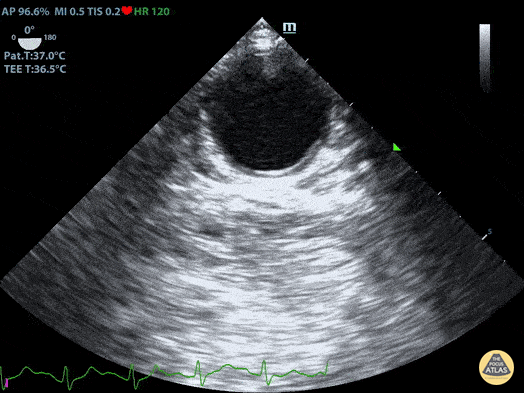

TEE Normal Aorta Short Axis Duncan McGuire, DO, Emergency Medicine, Beaumont Health

https://www.thepocusatlas.com/tee